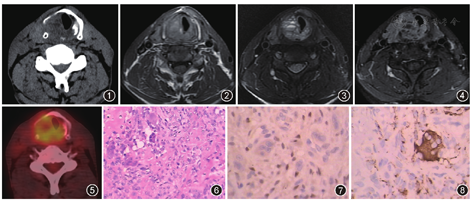

颈部CT检查:右侧声门下区可见类圆形3.3 cm×2.2 cm软组织密度影,密度不均,内见多发小片状低密度区,边界模糊,平均CT值为42 HU。病灶侵犯右侧甲状软骨板及环状软骨,其下缘跨越中线累及对侧(图1)。MRI检查:T1WI肿块信号稍高于颈部肌肉,内见多发小片状高信号,考虑为出血(图2);T2WI病变呈混杂高信号,内见多发结节状高信号,形似"蜂窝状",部分见液-液平面。病变累及对侧喉壁,信号与右侧类似(图3)。增强后肿块呈明显不均匀性强化,强化程度较甲状腺明显,内见多发囊状不强化区(图4)。PET-CT检查:右侧声门下肿块18F-脱氧葡萄糖摄取明显增高,最大标准摄取值(standardized uptake value,SUV)为4.2,左侧声门下区受累部位也呈类似改变(图5)。根据影像表现诊断:喉部占位,考虑为恶性。

手术及病理:于甲状腺右侧叶及环状软骨板下缘声门下见右侧喉室外生型白色新生物,质硬,钳夹后有少量出血。肿块向前累及甲状腺右侧叶,向后累及气管-食管沟。病变破坏右侧声带并侵犯对侧声带及第1气管软骨环,浸润深度达喉壁深肌层。病理检查:见肿瘤内大量梭形单核细胞,其间散在分布多核巨细胞(图6)。免疫组织化学染色:波形蛋白、P63单核细胞(图7)、PGM-1多核细胞阳性(图8),CK、结蛋白、平滑肌肌动蛋白、CD34、S-100均为阴性,Ki-67 10%。结合组织形态及免疫组织化学诊断为喉侵袭性巨细胞瘤。

喉巨细胞瘤在影像上多呈类圆形或不规则形的肿块,边界清楚或模糊,破坏邻近的喉软骨并侵及周围软组织或喉室。CT平扫密度不均匀,低于颈部肌肉,可以有明显钙化。MRI显示肿块呈膨胀性破坏,T1WI上呈等或高信号、T2WI呈不均匀高信号、增强扫描肿块明显强化[5]。本例影像表现有2个特点:(1)MRI上与发生于四肢长管状骨的表现有相似之处,肿瘤内部呈"蜂窝状",部分可见液-液平面;(2)对脱氧葡萄糖的摄取明显增高,与恶性肿瘤非常相似。这两个特点尚未见相关文献报道,需要更多的病例来证实。